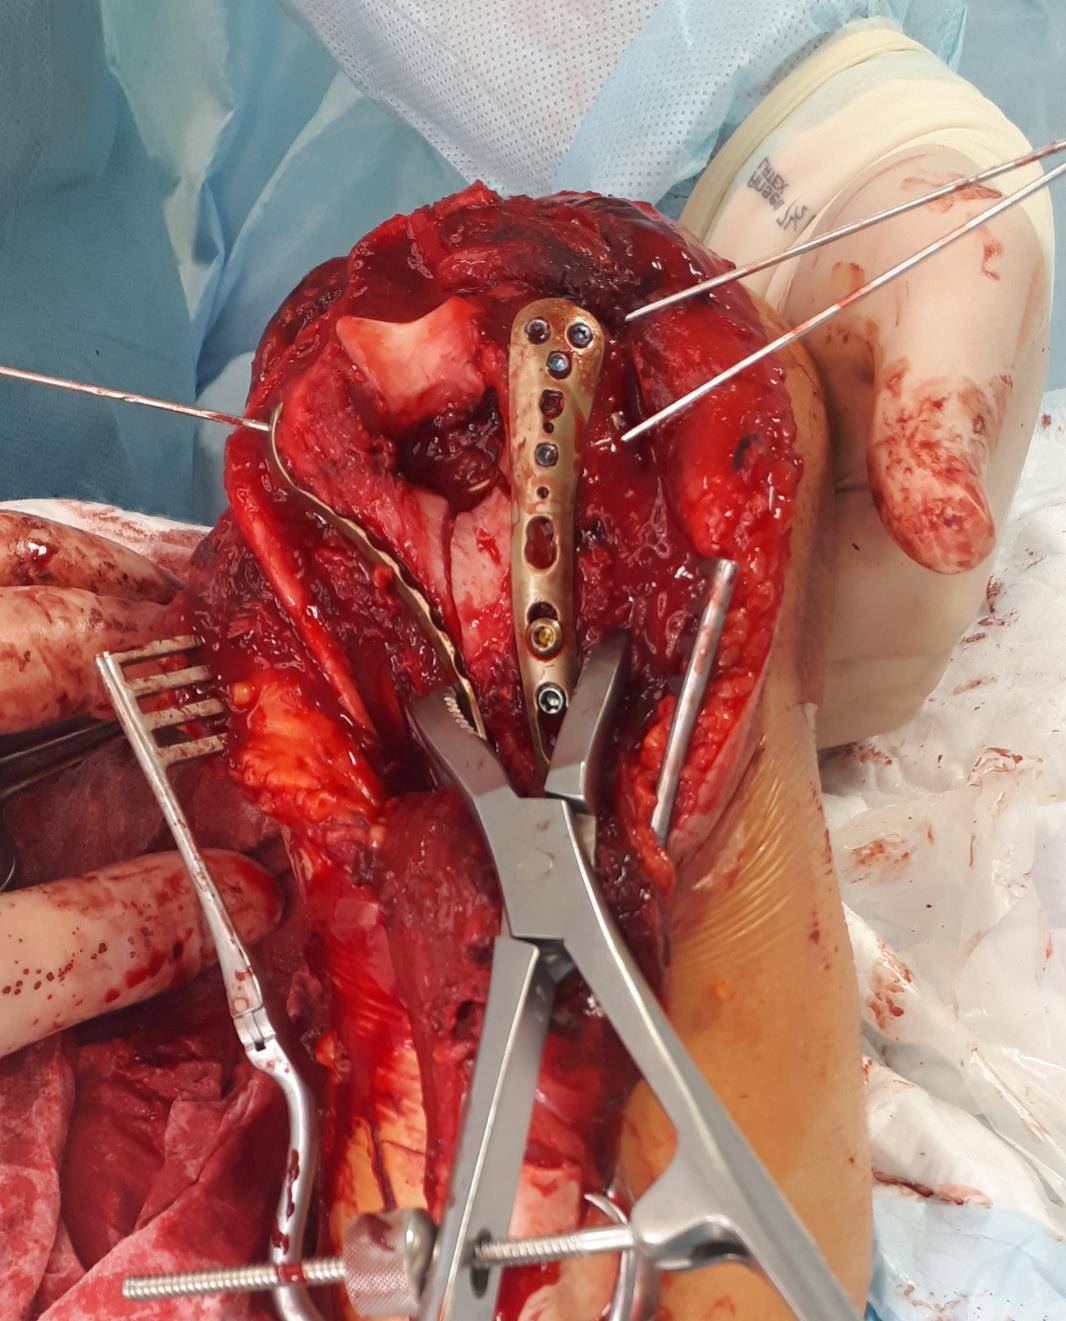

Для адекватной визуализации чаще всего используется доступ с остеотомией локтевого отростка, так как он обеспечивает максимально хорошую визуализацию как мыщелков плеча так и всего блока плечевой кости. При этом доступе производится шевронная остеотомия локтевого отростка, который после выполнения остеосинтеза мыщелков плеча фиксируется спицами и проволочной петлёй по Веберу.

После выполнения остеотомии и бережной сепарации сухожилия трицепса, необходимо выделить локтевой нерв и взять его на держалку, для профилактики его повреждения при выполнении остеосинтеза.

В первую очередь восстанавливается суставная поверхность. При отсутсвии сминания кости, или утерянных фрагментов, блок и головчатое возвышение могут быть соединены 2 компрессирующими винтами. Сначала фрагменты временно фиксируются спицами киршнера и костными цапками, так называемая прелиминарная фиксация.

Следующим этапом уже «собранный» блок фиксируется к медиальной и латеральной колоннам спицами, а потом уже вся эта конструкция при помощи пластин фиксируется к диафизу плечевой кости.

В том случае, когда вы имеете дело с оскольчатым переломом мыщелков плеча, хочется иметь максимально крепкие и надёжные импланты, которые обеспечат максимальную стабильность конструкции даже в условиях остеопорозной, рыхлой кости. Премоделированные анатомичные пластины фирмы Synthes отлично подходят для этой цели.

После установки винтов спицы удаляются, так как они уже выполнили свою функцию. Перелом мыщелков плеча надёжно фиксирован винтами и двумя пластинами с угловой стабильностью.

Последним этапом выполняется остеосинтез остеотомированного локтевого отростка спицами и проволочной петлёй по Веберу и послойное ушивание раны.